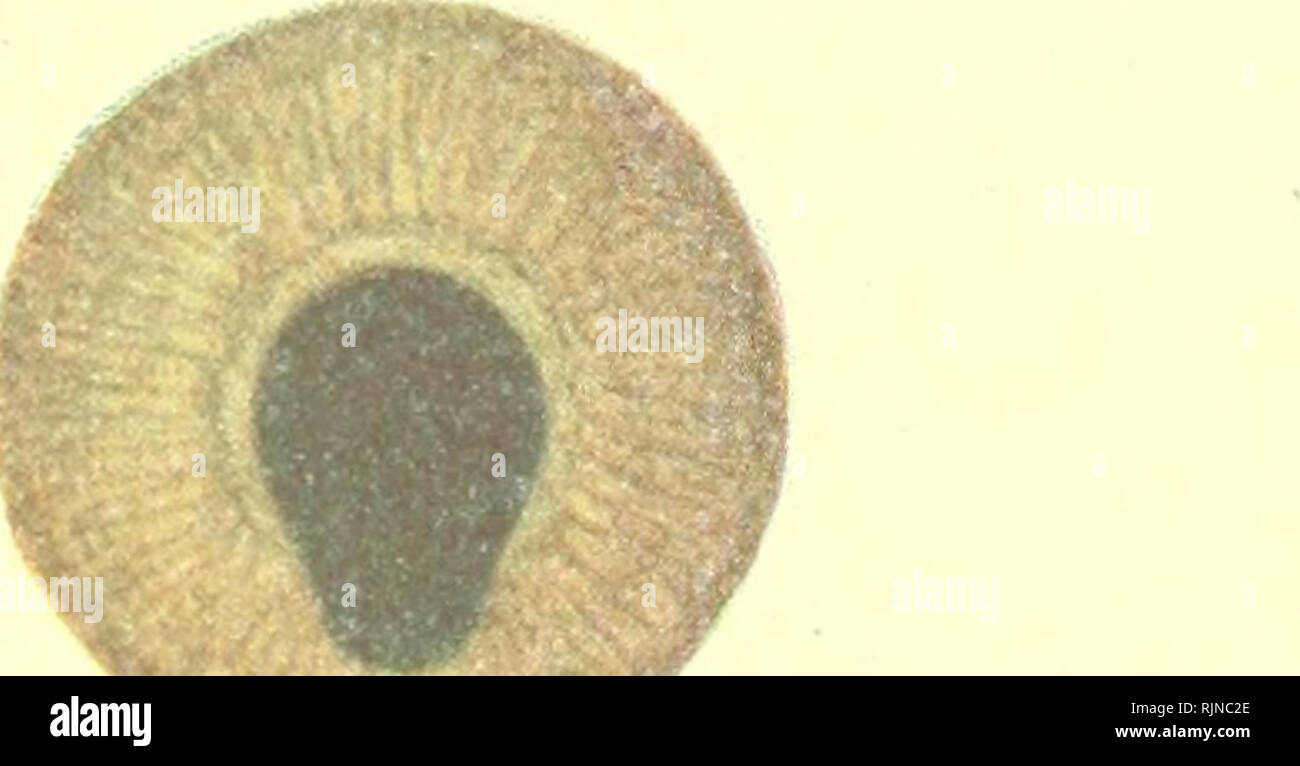

Fig. 4 A) Preoperative image of the right left(normal) eye, before

Fig. 4 A) Preoperative image of the right left(normal) eye, before What Is Polycoria Of The Eye Surgery can help some people with true polycoria. This can cause poor, dim or double vision. People with “true” polycoria have two or more separate pupils in one or both eyes. Each pupil has its own sphincter muscle and they individually constrict and dilate. Polycoria is a rare ocular condition characterized by the presence of two or more pupils within. What Is Polycoria Of The Eye.